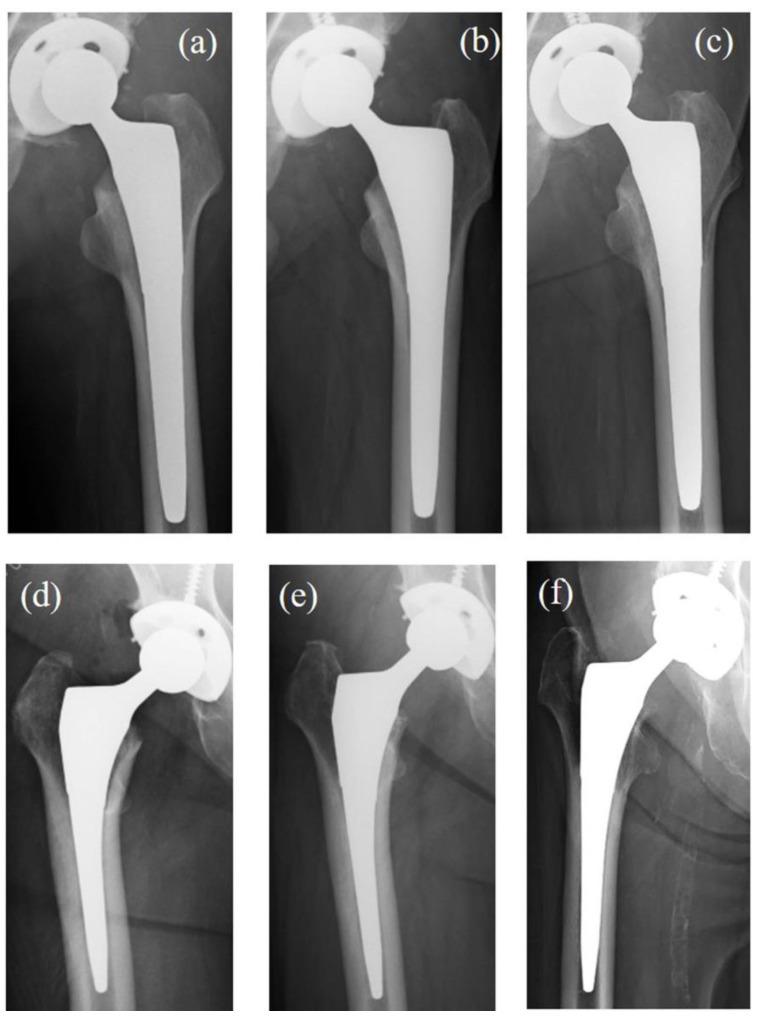

使用低杨氏模量Ti-33.6Nb-4Sn股骨柄预防应力遮挡的有效性:一项7年随访研究。

Effectiveness of Stress Shielding Prevention Using a Low Young's Modulus Ti-33.6Nb-4Sn Stem: A 7-Year Follow-Up Study.

Stress shielding (SS) after total hip arthroplasty (THA) leads to proximal femoral bone loss and increases the risk of complications such as implant loosening and periprosthetic fracture. While various low-stiffness stems have been developed to prevent SS, they often compromise mechanical stability. A novel femoral stem composed of Ti-33.6Nb-4Sn (TNS) alloy offers a gradually decreasing Young's modulus from proximal to distal regions, potentially improving load distribution and reducing SS. This study aimed to evaluate the mid-term clinical and radiographic outcomes of the TNS stem, with a particular focus on its effectiveness in suppressing SS.

A prospective clinical study was conducted involving 35 patients who underwent THA using the TNS stem, with a minimum follow-up of 7 years. Twenty-one patients with Ti6Al4V metaphyseal-filling stems served as controls. Clinical outcomes were assessed using Japanese Orthopaedic Association (JOA) scores, and radiographic SS was graded using Engh's classification and analyzed in Gruen zones. Inter-examiner reliability and statistical comparisons between groups were performed using appropriate tests.

The TNS group showed significantly higher preoperative JOA scores than the control group, but no significant difference in final scores. Both groups demonstrated significant improvement postoperatively. Third-degree SS occurred in the TNS group, although the overall SS grade distribution was significantly lower than in the control group ( = 0.03). SS frequency was significantly reduced in Gruen Zones 2, 3, and 6 in the TNS group.

The TNS stem demonstrated a significant reduction in SS progression compared to conventional titanium stems over a 7-year period, with comparable clinical outcomes. However, the occurrence of third-degree SS indicates that material optimization alone may be insufficient, highlighting the need for further design improvements.

全髋关节置换术(THA)后应力遮挡(SS)会导致股骨近端骨质流失,并增加植入物松动和假体周围骨折等并发症的风险。虽然已经开发出各种低刚度柄来预防SS,但它们往往会损害机械稳定性。一种由Ti-33.6Nb-4Sn(TNS)合金制成的新型股骨干,其杨氏模量从近端到远端区域逐渐降低,可能会改善载荷分布并减少SS。本研究旨在评估TNS柄的中期临床和影像学结果,特别关注其在抑制SS方面的有效性。

进行了一项前瞻性临床研究,纳入35例行TNS柄THA的患者,随访至少7年。21例使用Ti6Al4V干骺端填充柄的患者作为对照。使用日本骨科协会(JOA)评分评估临床结果,并使用Engh分类对影像学SS进行分级,并在Gruen分区进行分析。使用适当的测试进行组间的检查者间信度和统计比较。

TNS组术前JOA评分显著高于对照组,但最终评分无显著差异。两组术后均有显著改善。TNS组出现了三度SS,尽管总体SS分级分布显著低于对照组(P = 0.03)。TNS组Gruen分区2、3和6的SS发生率显著降低。

与传统钛柄相比,TNS柄在7年期间的SS进展显著降低,临床结果相当。然而,三度SS的发生表明仅材料优化可能不足,突出了进一步改进设计的必要性。